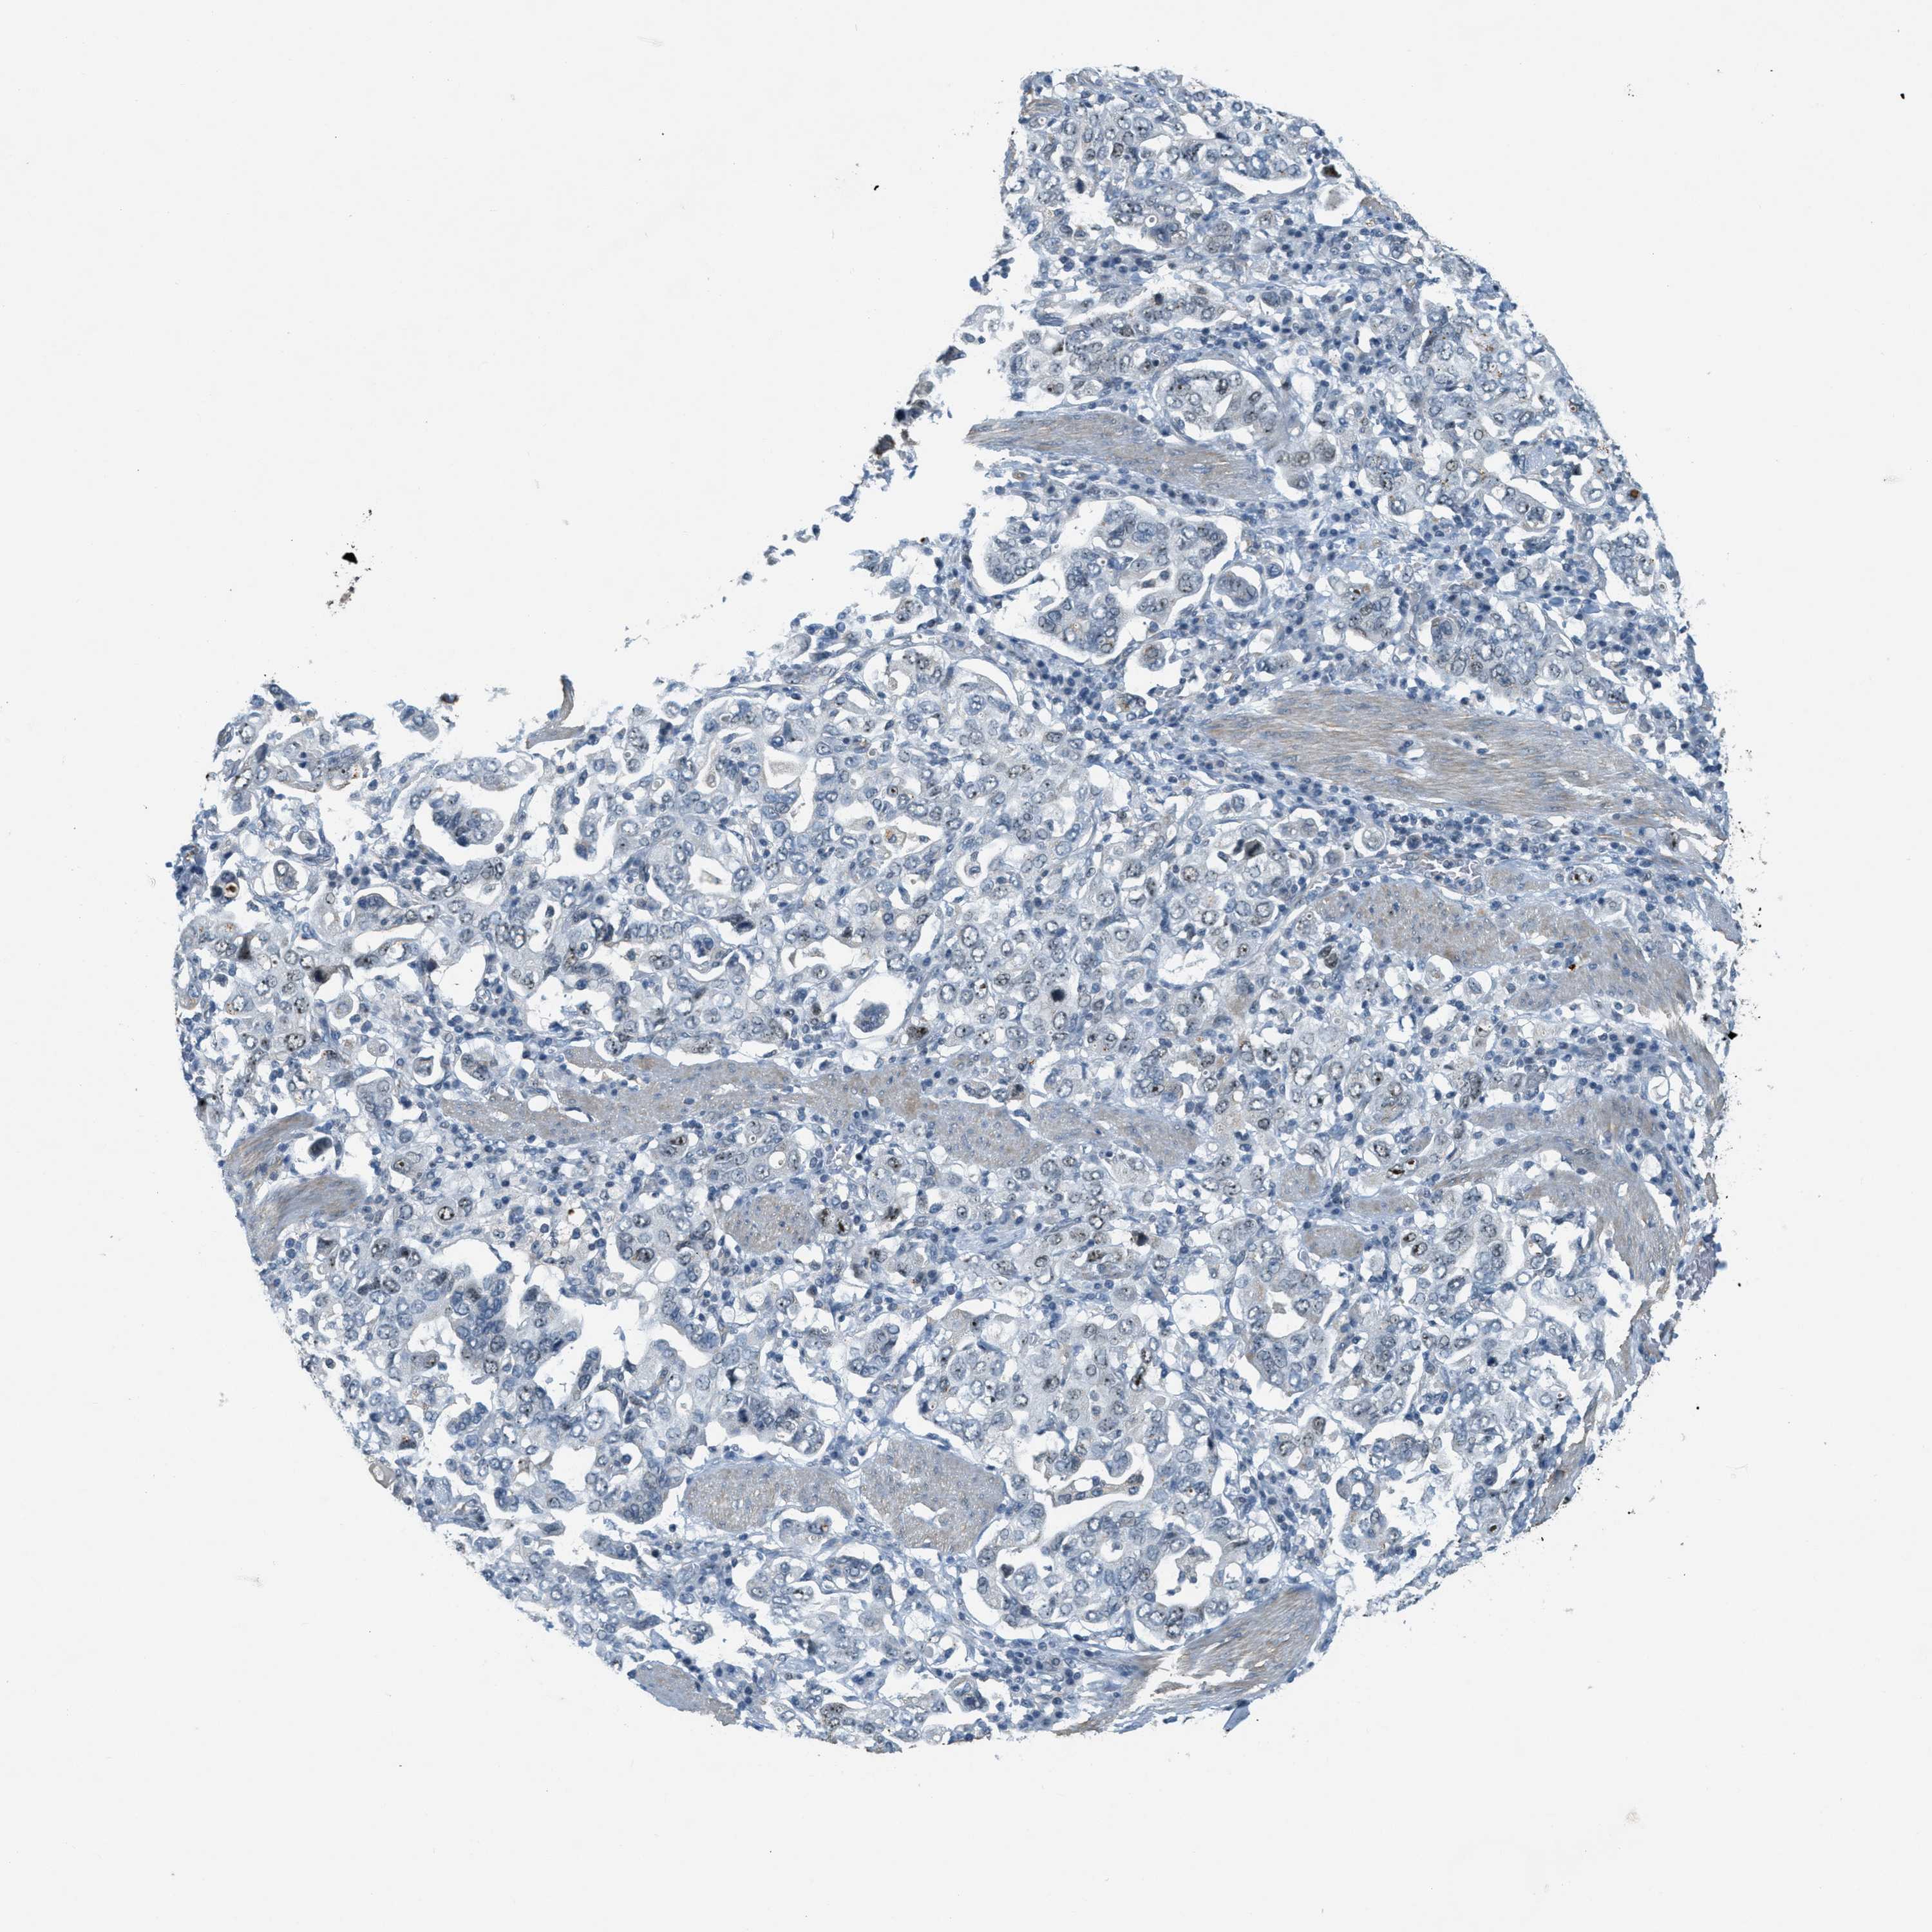

STOMACH CANCER - Protein expressioni

A mouse-over function shows sample information and annotation data. Click on an image to view it in a full screen mode. Samples can be filtered based on level of antibody staining by selecting one or several of the following categories: high, medium, low and not detected. The assay and annotation is described here.

Antibody stainingi

Antibody staining in the annotated cell types in the current human tissue is reported as not detected, low, medium, or high, based on conventional immunohistochemistry profiling in selected tissues. This score is based on the combination of the staining intensity and fraction of stained cells.

Each image is clickable and will lead to virtual microscopy that enables deeper exploration of all samples and also displays staining intensity scores, fraction scores and subcellular localization as well as patient and tissue information for each sample.

Antibody HPA014855

Staining

High

Medium

Low

Not detected

Intensity

Strong

Moderate

Weak

Negative

Quantity

>75%

75%-25%

<25%

None

Location

Nuclear

Cytoplasmic/membranous

Cytoplasmic/membranous,nuclear

Adenocarcinoma, NOS